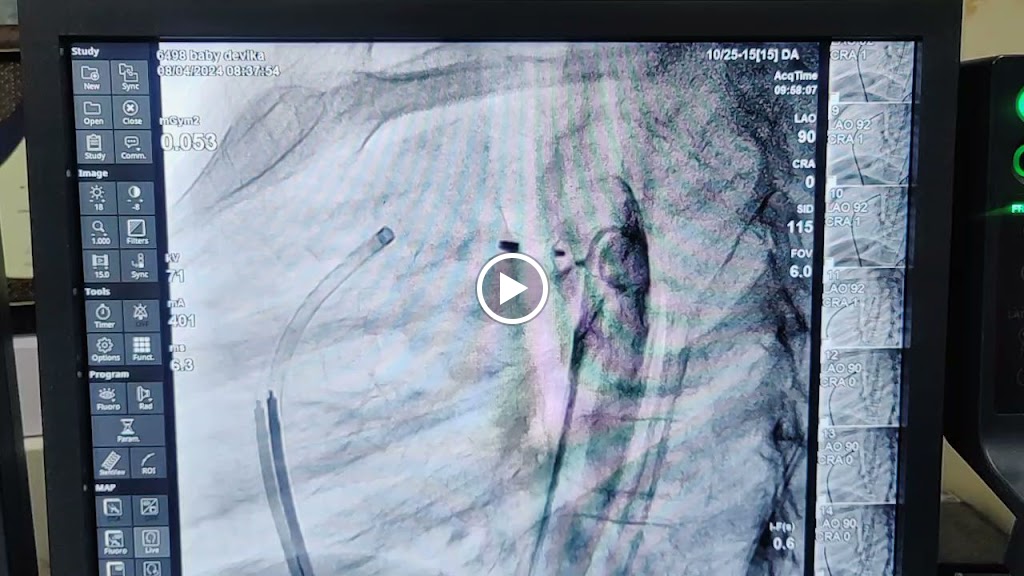

Office Gallery

Videos